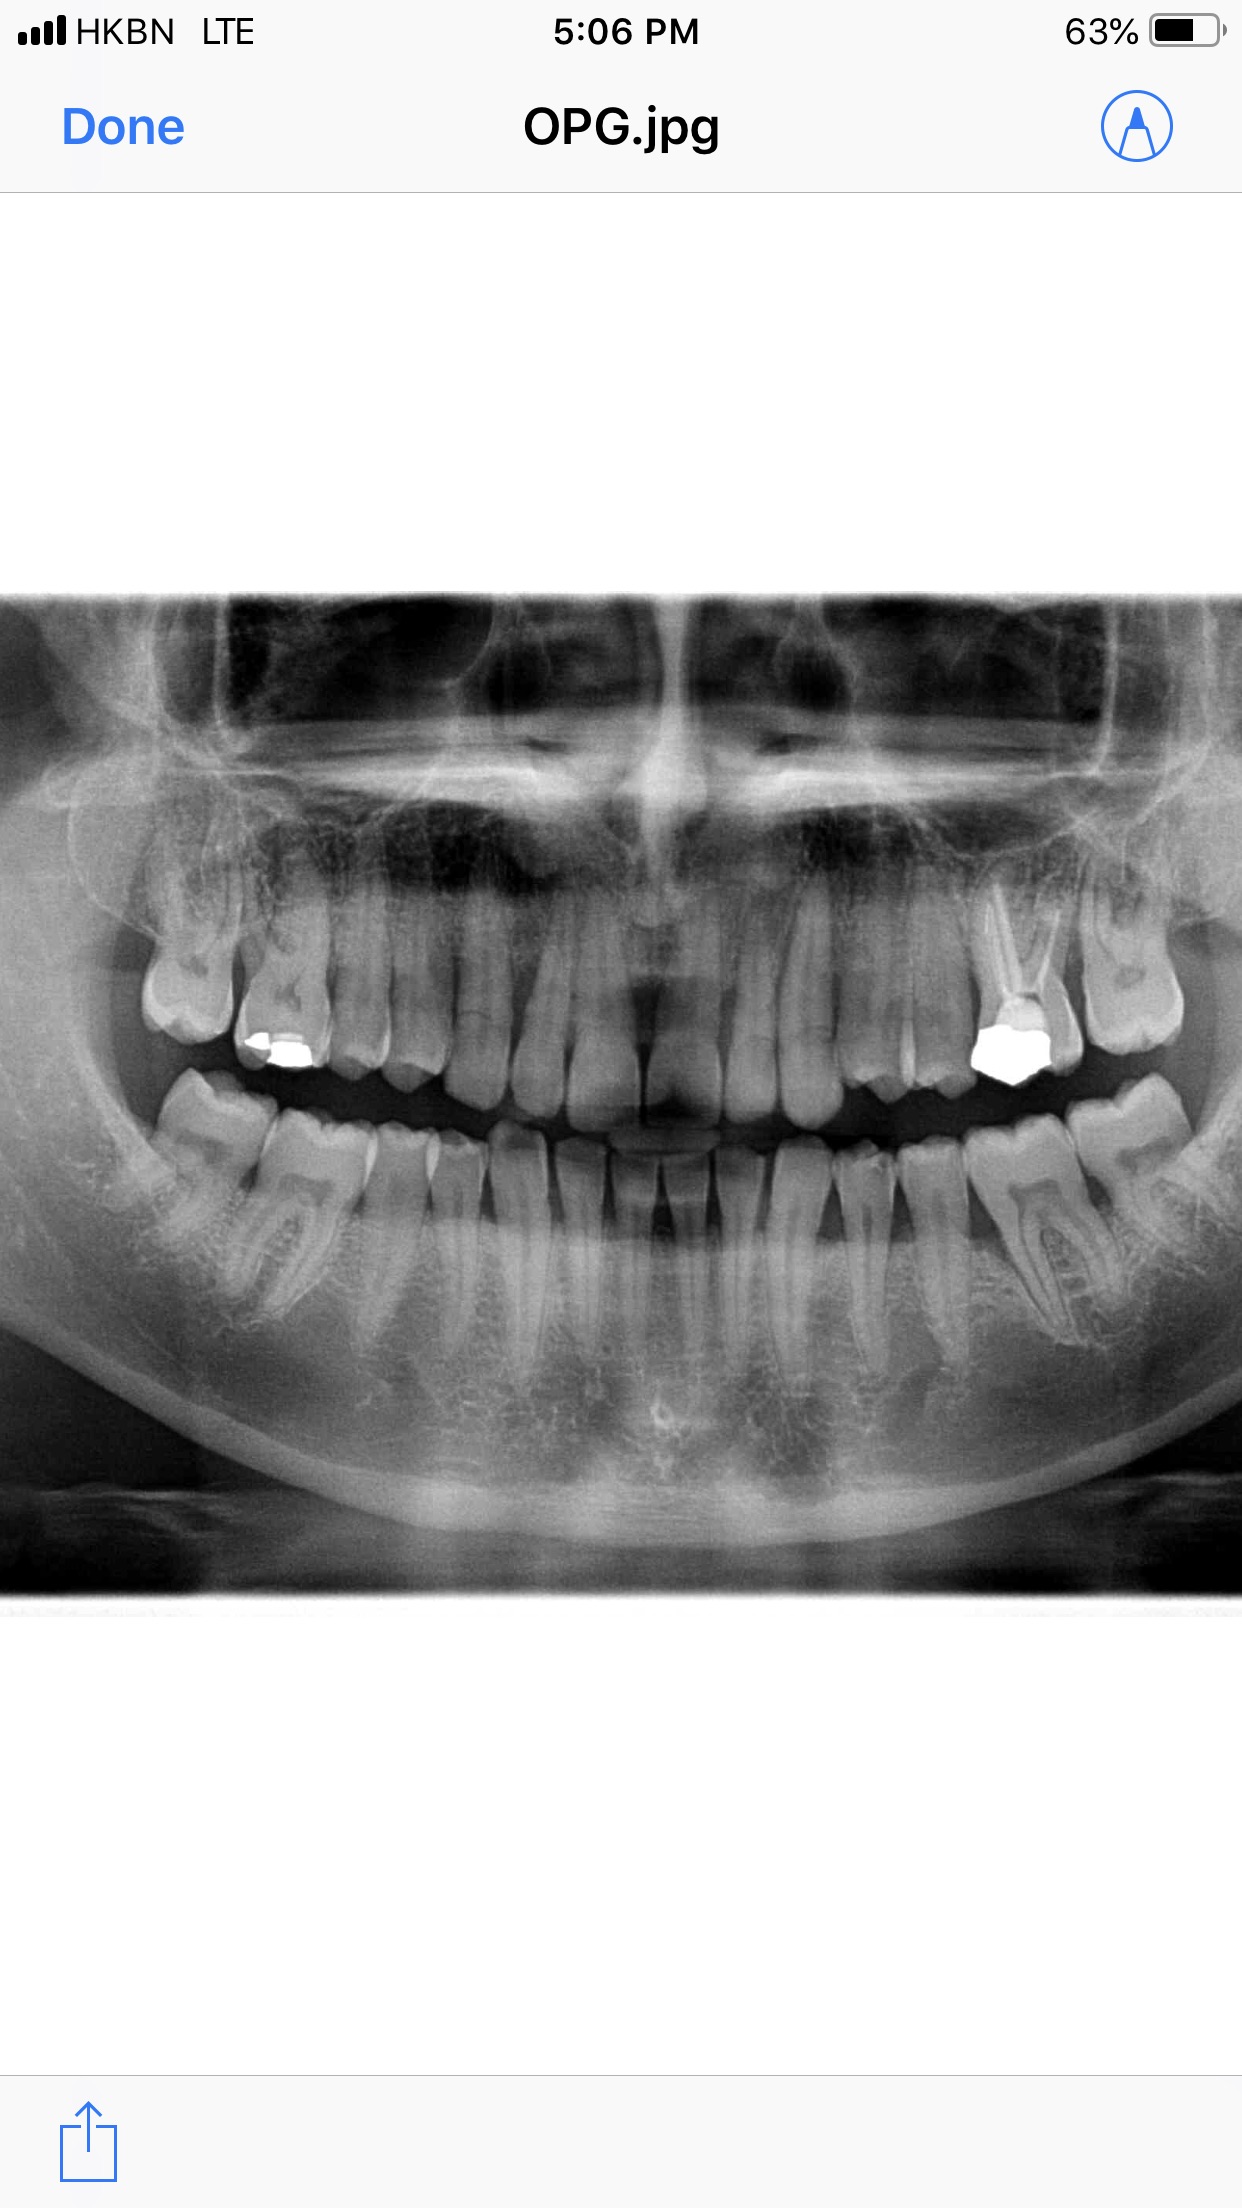

Needs clinical examination. on X-ray Examination RCT Of Upper 1-1 and splinting of teeth followered by deep curettage

I second Prof .asif are the steps initially we take to secure peridontally compromised mobile teeth .

I also see start of periapical infection in front teeth .

I must say to take one CBCT or periapical Xray for confirm diagnosis of infection .